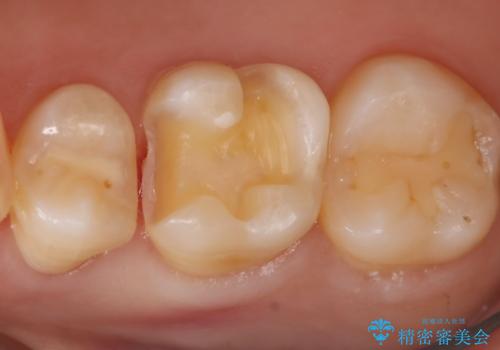

- 右上6番の虫歯治療を主訴に来院された患者様です。

切削量・形態を考慮し、セラミックインレーでの治療を計画しました。

保険の材料が劣化し中で虫歯が進行していたので、全て取り除いた上で形を整え型をとりインレーをセットしています。